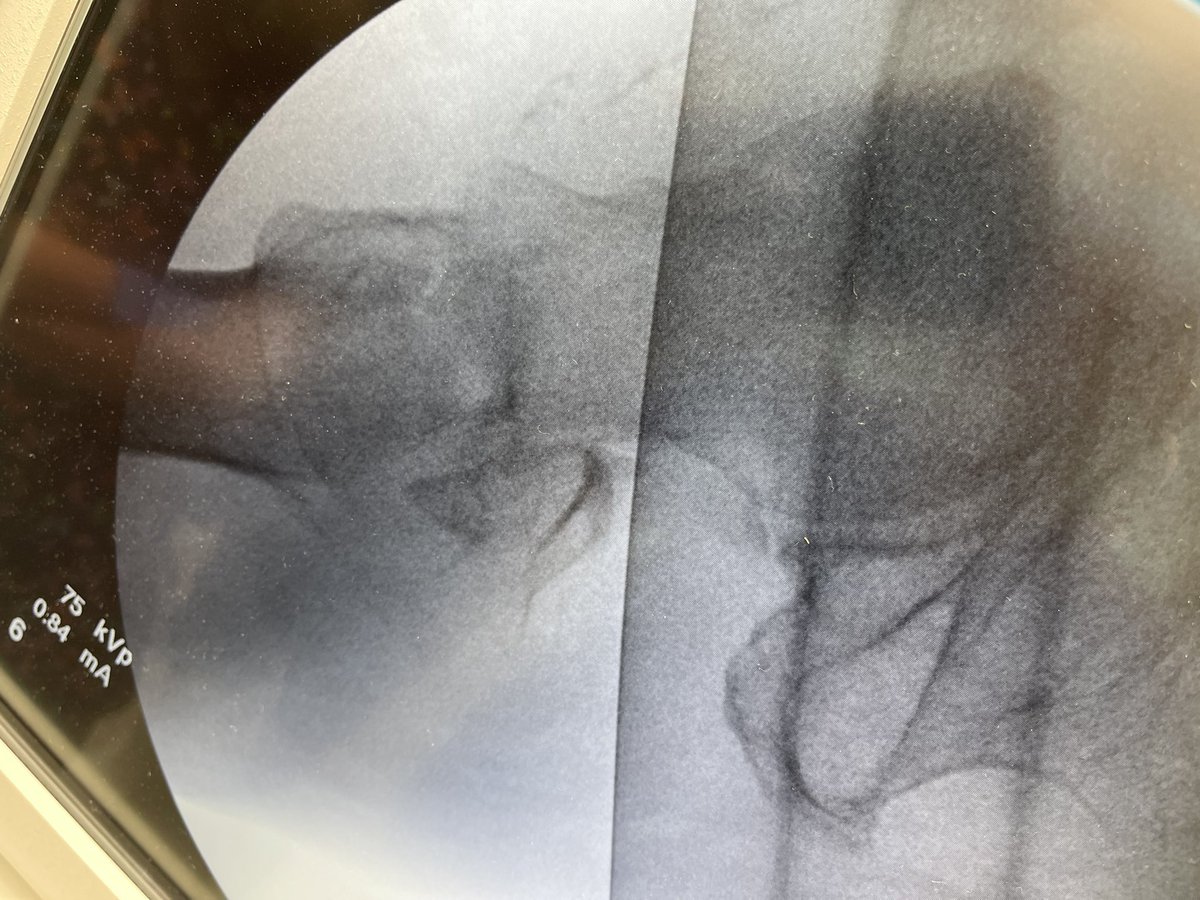

See what’s wrong here?

The large clamp across the ankle is not ‘reducing’ the syndesmosis, it is ‘over compressing’ it.

There is a reason we use Position screws across the syndesmosis and not Lag screws. Don’t over compress the syndesmosis, it will push/spit the Talus.